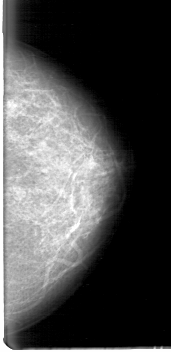

D_4067_1.LEFT_MLO

D_4067_1.LEFT_CC

LEFT_MLO LINES 5386 PIXELS_PER_LINE 3121 BITS_PER_PIXEL 12 RESOLUTION 43.5 NON_OVERLAY

LEFT_CC LINES 5266 PIXELS_PER_LINE 2551 BITS_PER_PIXEL 12 RESOLUTION 43.5 NON_OVERLAY